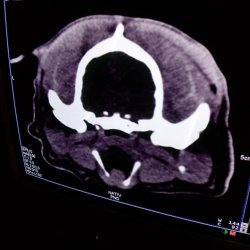

Jonášek je svěřenec dočaskářských tet. Trápila ho osina mezi prsty na přední tlapce, bohužel v jeho chlupatých nožkách nešlo nic moc vidět, a tak skončil v pondělí na veterině - poté, co mu opouzdřená osina praskla a nožka vyžadovala ošetření. Osina se ale nenašla, a tety Jonáška nechtěly bez sedace více trápit, tudíž se hned na čtvrtek domluvila sedace, v rámci které se noha chirurgicky zrevidovala, osina se našla a vytáhla. Současně se Jonášek hned vykastroval a bylo mu provedeno CT hlavy, vzhledem k jeho neurologickým příznakům a nestandartnímu chování.

CT vyšetření odhalilo, že Jonášek má velmi malý, zakrnělý mozek, jehož velikost je téměř stejná, jako velikost obou nosních dutin, tudíž se pravděpodobně jedná o vrozenou záležitost. Narozdíl od ostatních pejsků, kteří jsou zdraví, Jonáškovu větší část hlavy tvoří jen sval a podkoží. Tím bylo vysvětleno jeho zvláštní, zpomalené chování a občasná panika.Pro Jonáše budou tety hledat rodinku, kde ho přijmou takového, jaký je, nebudou po něm chtít žádné zázraky (jak říkají tety). Je to velmi hodný a klidný pejsek, který nevyžaduje žádné extra aktivní vyžití, bude mu stačit zahrádka, pohlazení a tolerantní člověkové okolo, kteří ho budou milovat. Nikdy nekousne, naučil se čistotnosti a chodí se i mazlit. S pejsky vyjde bez problémů, doma vydrží sám a neštěká, tedy, jakmile si zvykne.